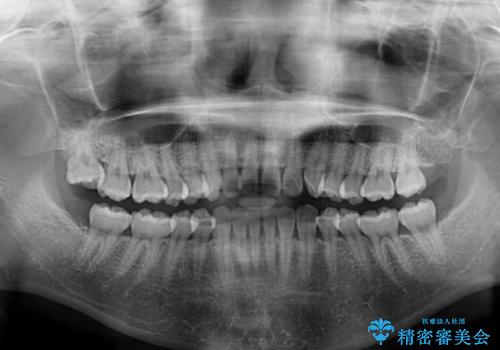

- 前歯のデコボコを治したいとのことで来院された患者様です。

上下顎ともに歯列全体の側方拡大とIPR(歯と歯の間を削る)によってデコボコが解消するように設計し、インビザラインにより治療を行うこととしました。

後方移動に際し、残っていた上顎の親知らずを抜歯することとしました。